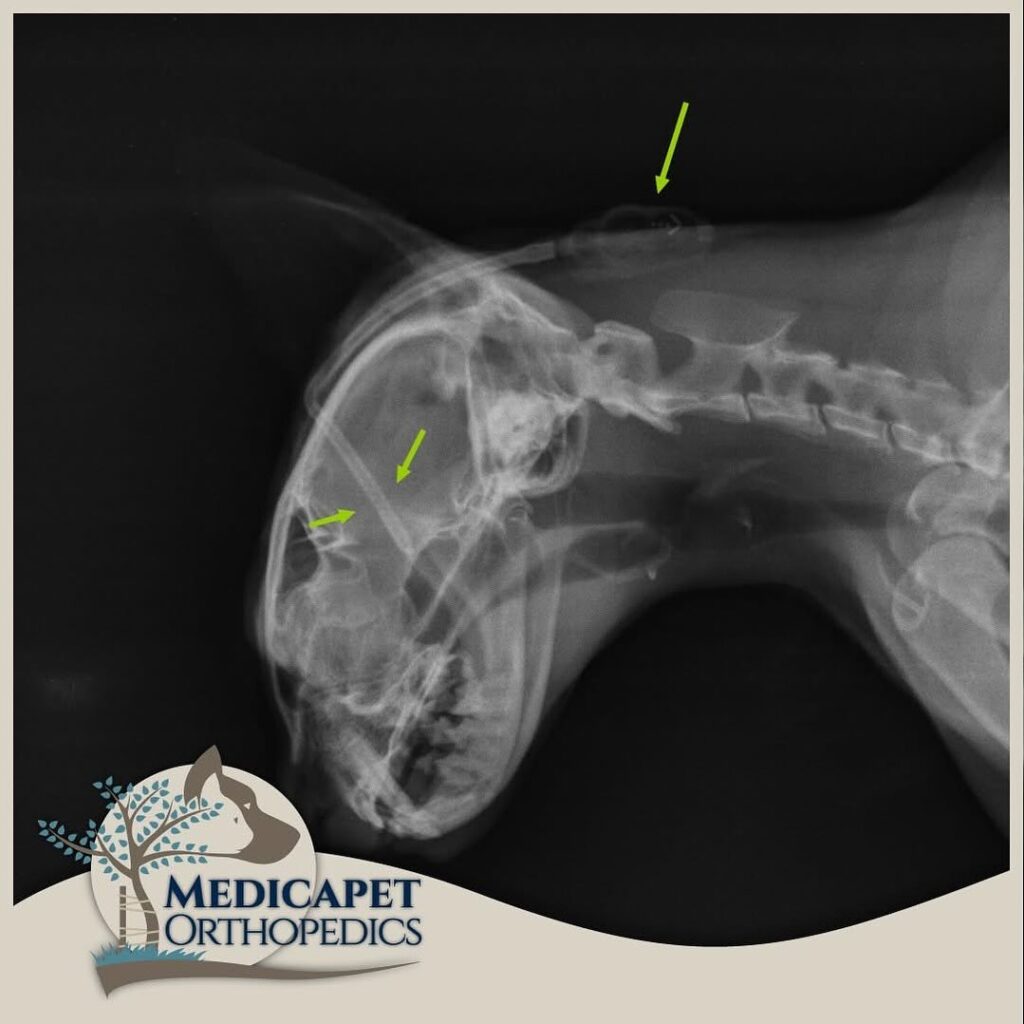

CERRAHİ TEDAVİ Ventriculoperitoneal Şant uygulamasını kapsar. Ventriküllerde üretilerek sistemik dolaşıma katılamayan ve beyine yüksek derecede basınç uygulayan BOS’un beyinden kalbe ya da karın boşluğuna aktarılmasını sağlayan bir sistemin yerleştirilmesi işlemidir. Yüksek seviyede tecrübe gerektiren bir operasyondur. Beynin içerisine yerleştirilen bir kateter ense kısmında deri altına yerleştirilmiş olan bir vanaya bağlanır. Bu otomatik slikon vana beyin içerisindeki basınç artınca açılarak kendisine bağlı olan diğer katetere fazla BOS sıvısını akıtarak karın boşluğuna ya da kalbe iletilmesini sağlar. Bu bölgelere gönderilen fazla BOS buralardan emilerek sistemik dolaşıma geçer ve vücut dışına atılır. Medicapet rutin olarak bu ameliyatı yapan Türkiye’deki bir kaç merkezden biridir. Hidrosefalinin cerrahi tedavisinde başarı oranımız oldukça yüksektir. Operasyon sonrasındaki iyileşme oranı, hastanın beyin dokusunun almış olduğu hasarın boyutuna ve ne kadarının reversbl olduğuna bağlıdır. erken müdahale edilen hastanın yaşamsal fonksiyonlarının ve yüksek yaşam standardının korunması daha olasıdır.